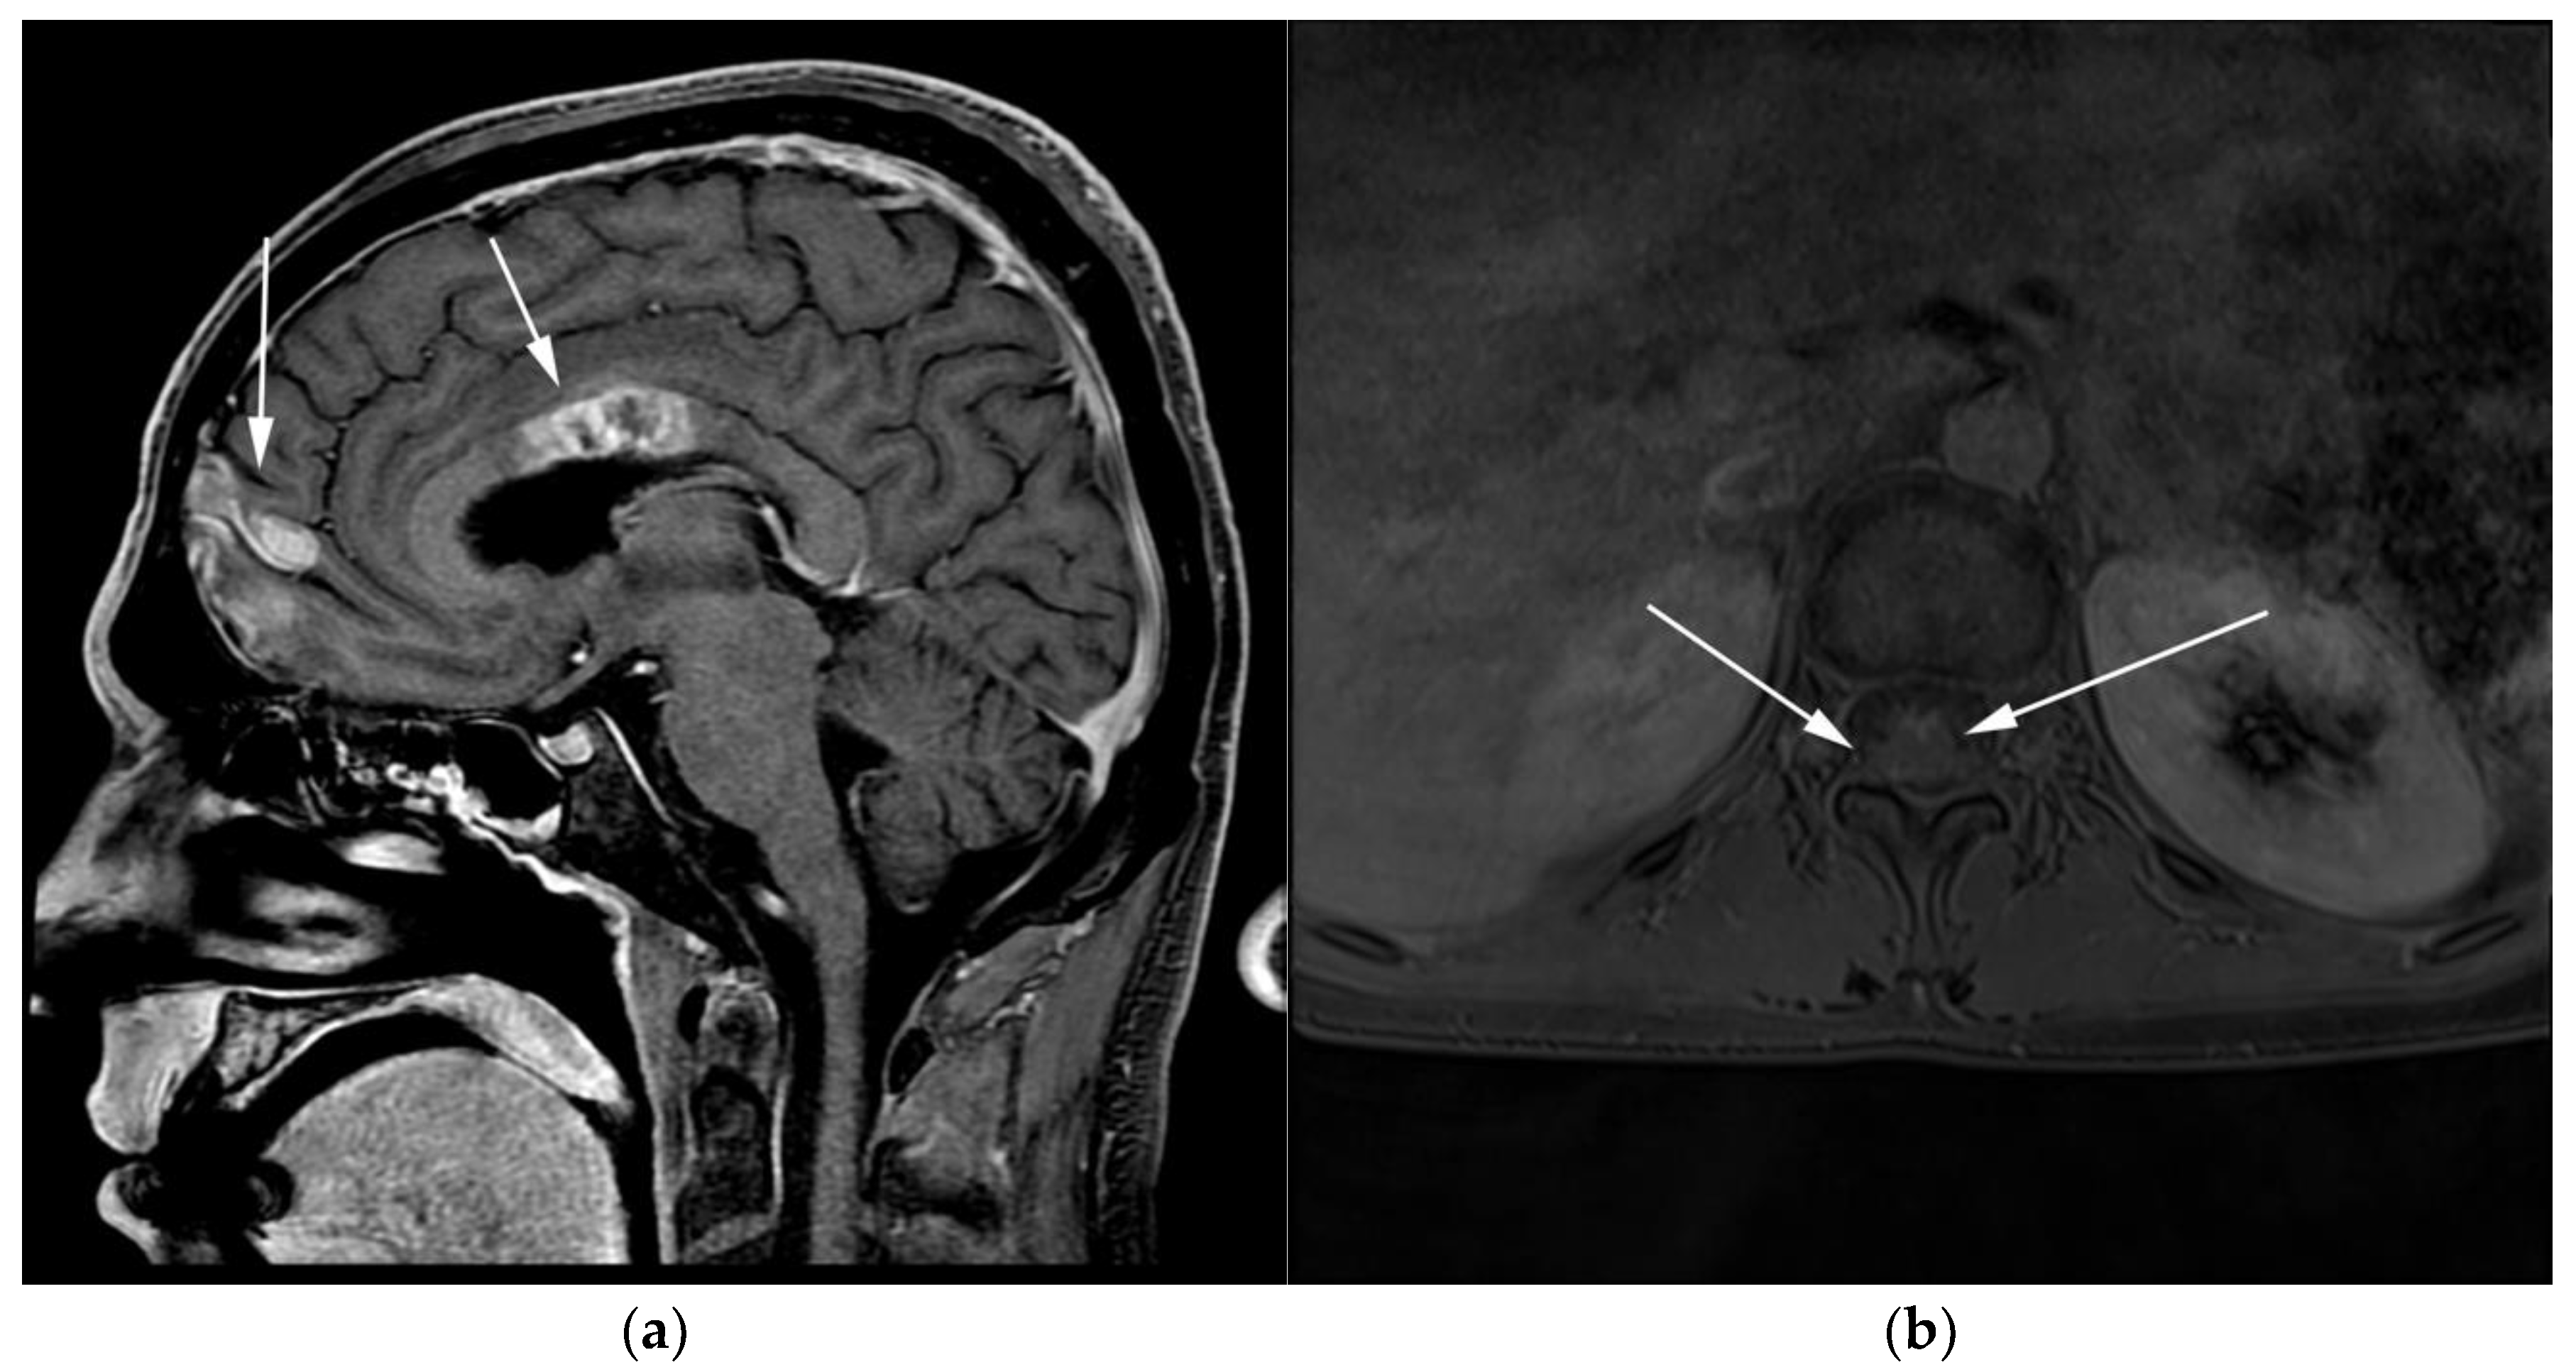

Figure 10.

Imaging in the same patient 1 year later—patient developed new brain and spine lesions. (a) Sagittal T1 post-contrast MRI images show heterogenous mass within the body of the corpus callosum (posterior arrows) as well as within the frontal cortex (anterior arrows). (b) Axial T1 post-contrast MRI of the spine shows ill-defined enhancement within the spinal cord (arrows), consistent with leptomeningeal disease.

Figure 13.

Patient with known diagnosis of lymphoplasmacytic lymphoma (LPL). (a) Coronal T1 post-contrast of the brain image shows diffuse leptomeningeal enhancement (black arrows). (b) Axial MRI T1 post-contrast image of the lumbosarcal spine in the same patient shows diffuse epidural soft tissue thickening and enhancement of the cauda equina nerve roots (white arrows). (c) Microscopic examination of the lymph node shows effaced architecture by infiltrative diffuse sheets of atypical lymphoid cells with plasmacytoid morphology. Tumor cells are positive for CD20 and are monotypic, expressing kappa or lambda light chains. (Original magnification 400×, H&E stain). CNS involvement in is an extremely rare variant known as Bing–Neel syndrome (BNS).